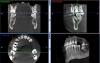

Slavik111 Опубликовано 5 июля, 2010 Автор Поделиться Опубликовано 5 июля, 2010 (изменено) Спасибо за ответ.Вот панорама.Вывод о том, что после удаления 16 и 17 образуется соустье, хирург сделал после просмотра 3Д снимка - это большая программа, ее сюда не закачать. Изменено 5 июля, 2010 пользователем Slavik111 Ссылка на комментарий

Slavik111 Опубликовано 5 июля, 2010 Автор Поделиться Опубликовано 5 июля, 2010 (изменено) Мне к сожалению снимки оттуда не выдернуть - это программа на диске которая сама демонстрирует свои снимки. Кажется формат DICOM. Но я попробую выдернуть (через копию экрана) пару продольных снимков этих зубов.Мне хирург сказал, что есть соустье или нет выяснится непосредственно после удаления. То естькак повезет. И если не повезет\, надо будет вскрывать пазуху и чистить гной перед ушиванием.Отличается ли эта операция по чистке от ЛОР операции на пазухе? (менее травмотична?)Можно ли при наличии какого-то минимального кол-ва гноя вообще не чистить пазуху у стоматолога, а просто - удалить, если соустья - зашить и пойти к ЛОРу промывать пункцией? Изменено 5 июля, 2010 пользователем Slavik111 Ссылка на комментарий

Slavik111 Опубликовано 5 июля, 2010 Автор Поделиться Опубликовано 5 июля, 2010 (изменено) Названия файлов - номера зубов. Еще 17-й зубhttp://saveimg.ru/show-image.php?id=b293d8...a9dc1c7d74bba31http://saveimg.ru/show-image.php?id=8c6420...92ba92c9a149318http://saveimg.ru/show-image.php?id=0660de...848084cfe5e2b22 Изменено 5 июля, 2010 пользователем Slavik111 Ссылка на комментарий

Slavik111 Опубликовано 6 июля, 2010 Автор Поделиться Опубликовано 6 июля, 2010 Согласен. + Все может оказаться еще проще, удалят, сообщения не будет, гайморит пройдет быстро. Насчет сообщения - я специально 4 снимка 17-го зуба приложил - там с моей точки зрения корни прямо в пазуху торчат (если это однородное пространство над корнем - пазуха).Или я не прав и это не пазуха? Большое спасибо за советы! Только что был на приеме у ЛОРа. 9-я пункция - вытянула немного (может 5 мл) шприцом желтого полупрозрачного секрета - сказала что киста. Затем промывала долго - 2 банки вылила - гной только вначале, примерно 1 чайная ложка (может меньше). По сравнению с позапрошлым разом - гораздо меньше.Извините, уважаемые, но несмотря на Ваши советы подписал отказ от госпитализации.След. пункция в четверг. ЛОР сердилась за мой отказ,сказала что меньше гноя уже не будет, но затем смягчилась (потому что ничего больше у меня не болит и насморка нет) и сказала что решим по результатам пункции в четверг.На самом деле я буду думать - я понимаю что в стационаре лучше, но раз все-таки меня соблазнили "более легким" путем - если без гноя то амбулаторно - то получается есть из чего выбирать. В черьверг, чувствую, уже не будет из чего выбирать Ссылка на комментарий